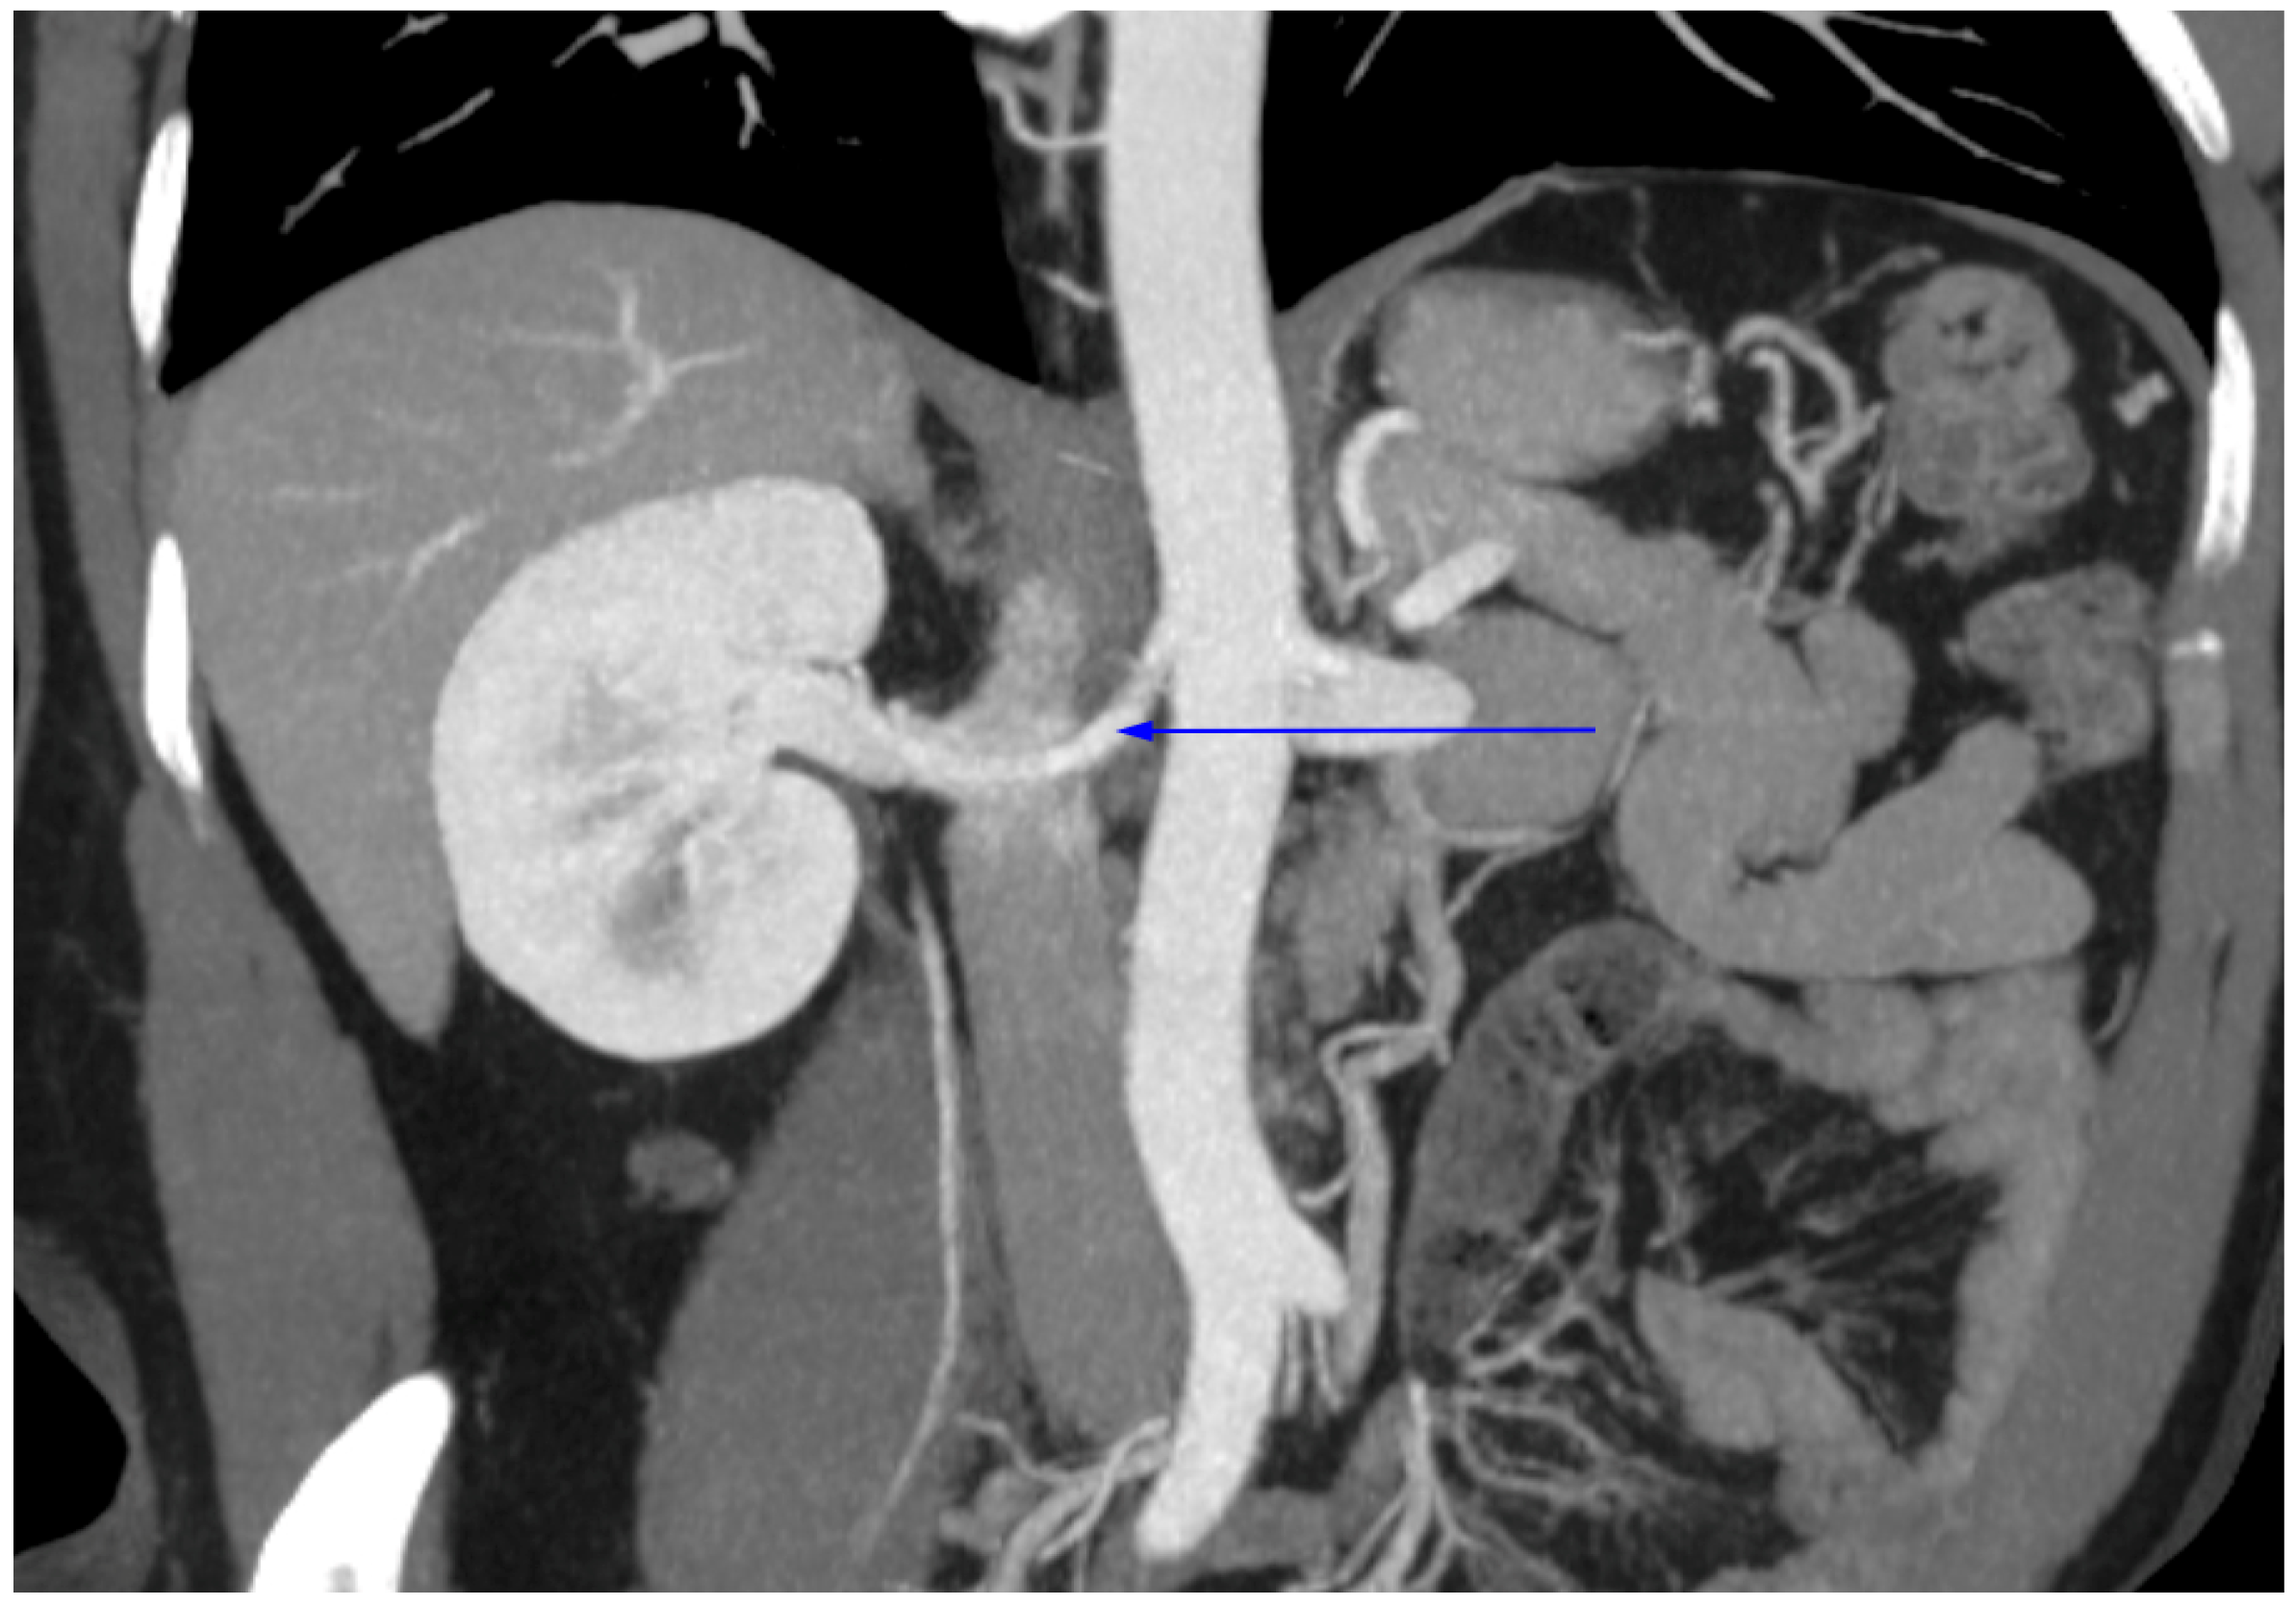

| Single left RV, anterior to aorta | 88 | 32 | 120 |

| Circumaortic with both trunks | 1 | - | 1 |

| Retroaortic | 3 | 4 | 7 |